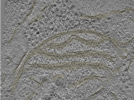

Photo Caption: Central slab from a representative tomogram of a Homo sapiens sample with selected set of annotations.

Cryo-electron tomography of FIB-milled HeLa PINK1-GFP cells treated with 10 uM Gamitrinib-triphenylphosphonium (G-TPP) for 4 hours to induce mitochondrial proteostatic stress. Data includes raw tilt series movie frames, assembled tilt series, tomographic reconstructions (WBP with and without CTF deconvolution), and automated segmentations of membranes. Acquired on a Titan Krios G4 with Falcon 4i detector and Selectris energy filter at 300 kV using dose-symmetric tilting with 3 degree increments. Cryo-FIB milling was performed on an Aquilos 2 cryo-FIB/SEM to produce lamellae of less than 250 nm thickness.